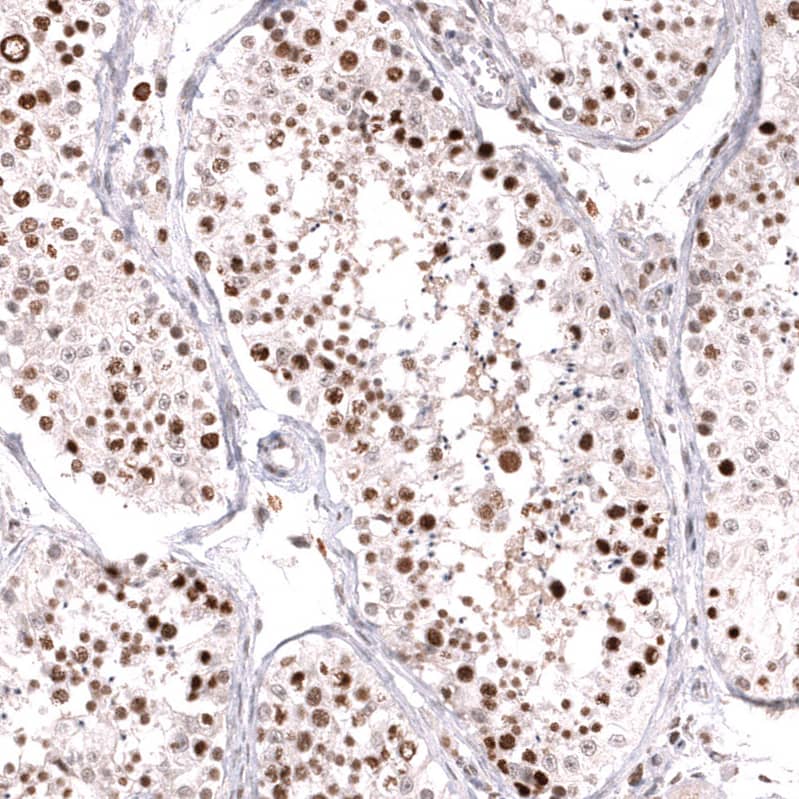

Staining of human testis shows strong nuclear positivity in cells in seminiferous ducts.